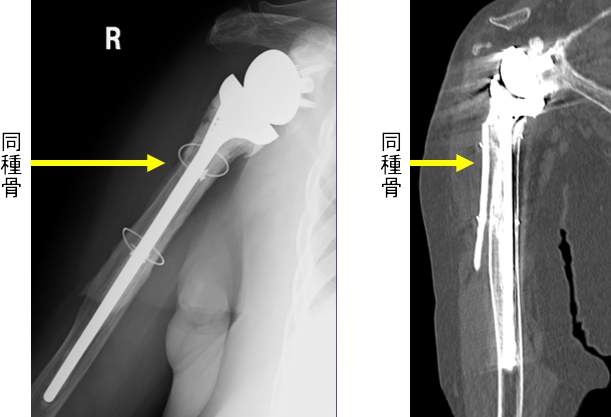

手術3年

同種骨は3年たっても上腕骨に固定され、ステムは上腕骨にしっかり固定されています